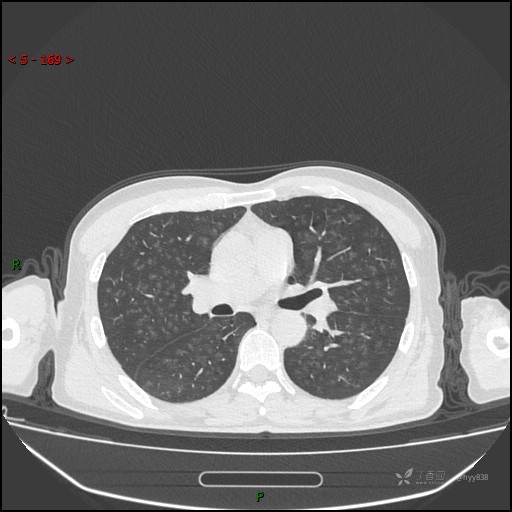

性别:男

年龄:55岁

简要病史:渐进性呼吸困难。

实验室检查:血象正常。

临床诊断:呼吸困难待查

胸部CT平扫